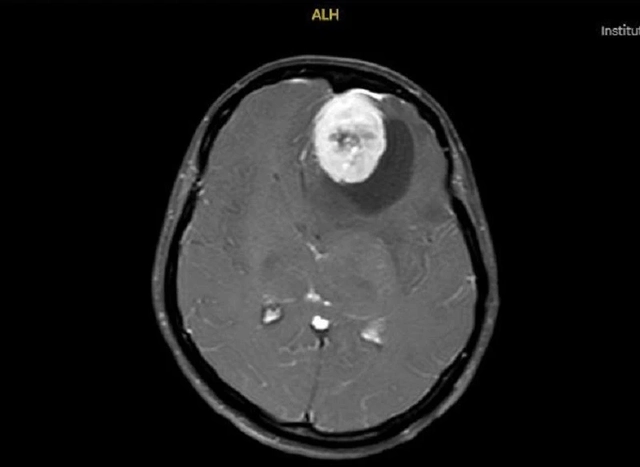

Các bác sĩ đã thực hiện thành công cuộc phẫu thuật bóc tách khối u màng não cho người bệnh

Ca phẫu thuật được triển khai với sự hỗ trợ của kính vi phẫu - thiết bị giúp phẫu thuật viên quan sát rõ những cấu trúc não sâu và phức tạp mà mắt thường khó nhận biết. Nhờ hình ảnh phóng đại sắc nét, bác sĩ có thể xác định ranh giới giữa khối u và mô não lành, lựa chọn đường mổ phù hợp, giảm tối đa xâm lấn và bảo tồn các mạch máu, cấu trúc thần kinh quan trọng.

Trong suốt hơn 4 giờ phẫu thuật, từng thao tác bóc tách được thực hiện cẩn trọng và chính xác. Kết quả, khối u đã được lấy trọn vẹn mà không gây tổn thương mô não xung quanh.